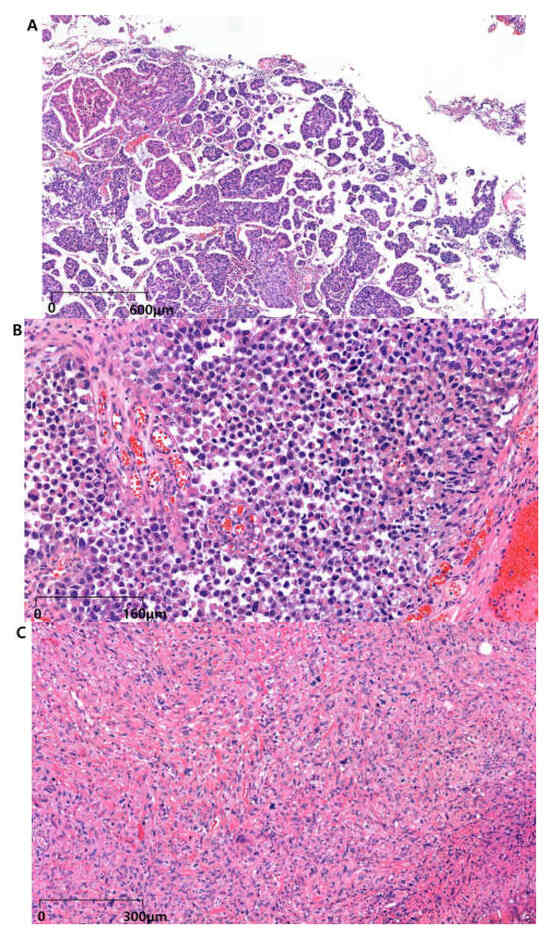

MPUC is a rare and highly aggressive subtype of UC, accounting for approximately 0.01–2.2% of urothelial tumors [46]. Histologically, MPUC is characterized by tight infiltrative clusters of micropapillary aggregates. These aggregates are frequently associated with vascular and lymphatic invasion, contributing to significant metastatic potential and adverse clinical outcomes (Figure 1A) [10]. First described in 1994 at the MD Anderson Cancer Center, MPUC demonstrates morphological similarities to ovarian papillary serous tumors, which is significant because of their shared aggressive behavior and poor prognosis, suggesting potential parallels in treatment approaches [47]. It typically presents at an advanced stage and is characterized by small nests of tumor cells within the lacunae, often lacking vascular cores, and it is accompanied by extensive lymphovascular invasion. Despite its aggressive nature, definitive histopathological criteria for MPUC remain controversial, further complicating its diagnosis and subsequent management [48].

Figure 1.

(A) Micropapillary subtype of UC (H&E); multiple small nests of tumor cells with surrounding lacunar (empty) space are a classic feature and may be the most helpful feature in making the diagnosis. (B) Plasmacytoid subtype of UC (H&E); discohesive single cells with eccentrically placed nuclei and abundant eosinophilic cytoplasm, which are often deeply infiltrative but with minimal stromal reaction. (C) Sarcomatoid urothelial carcinoma (H&E); malignant spindled cells with a nonspecific morphologic appearance and a mesenchymal-like growth pattern. The most common component is an undifferentiated high-grade spindle cell sarcoma, as in this figure. (D) Bladder squamous cell carcinoma (H&E); keratinization and intercellular bridges, features consistent with squamous differentiation. (E) Neuroendocrine bladder cancer (H&E); small, round cells with a high nuclear-to-cytoplasmic ratio, hyperchromatic nuclei, and fine chromatin, typical of neuroendocrine differentiation. (F) Bladder adenocarcinoma (H&E); prominent glandular formation of columnar cells and potential mucin production, raising the differential diagnosis of spread from the gastrointestinal tract or other primary sites. Abbreviations: UC, urothelial carcinoma; H&E, hematoxylin and eosin.